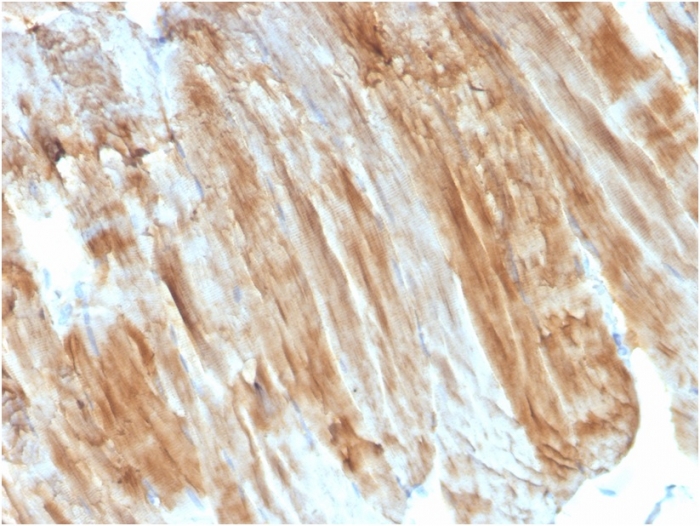

Formalin-fixed, paraffin-embedded human Skeletal Muscle stained with Dystrophin Monospecific Mouse Monoclonal Antibody (DMD/3243).

Dystrophin-glycoprotein complex (DGC) connects the F-Actin cytoskeleton on the inner surface of muscle fibers to the surrounding extracellular matrix, through the cell membrane interface. A deficiency in this protein contributes to Duchenne (DMD) and Becker (BMD) muscular dystrophies. The human dystrophin gene measures 2.4 megabases, has more than 80 exons, produces a 14 kb mRNA and contains at least 8 independent tissue-specific promoters and 2 poly A sites. The dystrophin mRNA can undergo differential splicing and produce a range of transcripts that encode a large set of proteins. Dystrophin represents approximately 0.002% of total striated muscle protein and localizes to triadic junctions in skeletal muscle, where it is thought to influence calcium ion homeostasis and force transmission.